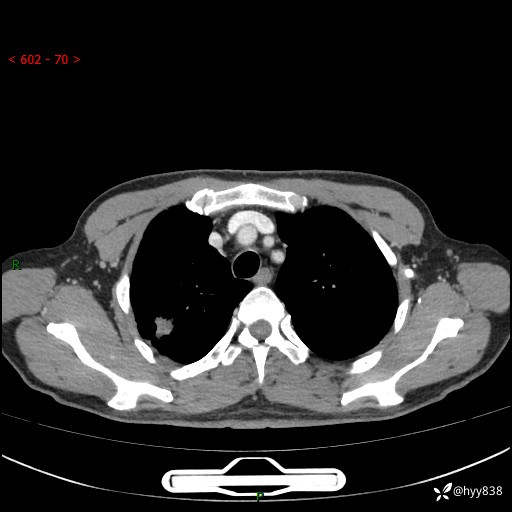

69岁/男,发现肺部病变6天。该有的征象都有,肉芽肿 VS 肿瘤,一念之间---(有结果)

主诉:发现肺部病变6天。

现病史:患者6天前于我院泌尿外科住院,住院期间行胸部CT检查,提示“肺部病变”,患者无畏寒、发热、盗汗、咳嗽、咳痰、咯血、胸痛、呼吸困难,无反酸、腹痛、腹泻、头痛、头晕等不适。未予特殊处理,现为进一步诊治,门诊以“肺肿物”收入我科。 患者本次起病以来,精神食欲尚可,大小便正常,体力及体重无明显变化。

胸部CT平扫+增强